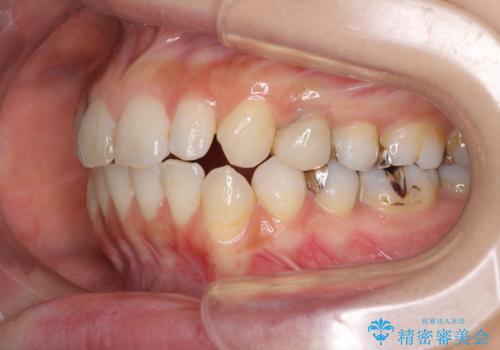

複数歯の補綴治療を行う場合、仮歯やセラミッククラウンを装着する度に保定装置を作り替える必要があり、その度に後戻りを起こす可能性が高くなります。

インビザラインであれば、矯正治療後半で補綴治療を行い、その後矯正治療を継続することでスムーズに治療を終えることができます。